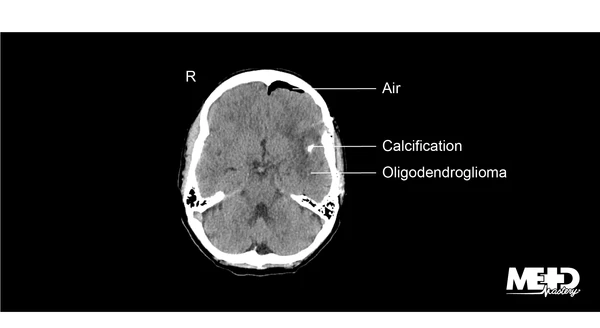

It can help to find where the tumour is and whether it has spread. CT scans also may be used to detect bone and vascular irregularities brain tumors and cysts brain damage from head injury hydrocephalus brain damage causing. A computerized tomography CT scan of the head is an imaging test that is sometimes used to confirm a brain tumor diagnosis.

A CT scan can help find bleeding and enlargement of the fluid-filled spaces in the brain called ventricles. A combined PETCT exam fuses images from a PET and CT scan together to provide detail on both the anatomy from the CT scan and function from the PET scan of the brain. A ct scan will show brain tumors if they are large enough have calcium or blood in them or are causing swelling.

A CT of the brain may be performed to assess the brain for tumors and other lesions injuries intracranial bleeding structural anomalies eg hydrocephalus infections brain function or. CT scans also show greater features of the bone structures near the tumor. Avoid Scanxiety by Preparing and Learning What to Expect Before During and After.

Learn the major indicators now. Unlike a regular x-ray a CT scan creates detailed images of the soft. A CT scan uses x-rays to make detailed cross-sectional images of your brain and spinal cord or other parts of the body.